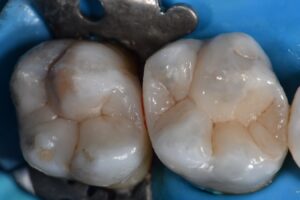

Home/Blog / Matrix in a Matrix approach to rebuilding a free end Class II situation

#VocoGrandioSO #MatrixinMatrix #GarrisonFirmBand